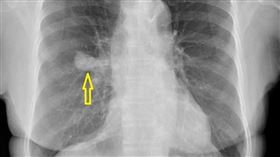

她2年沒健檢突胃痛 麻醉醫1個move揪肺癌

想要預防癌症,最有效的招式就是「檢查」。南部一名七旬...